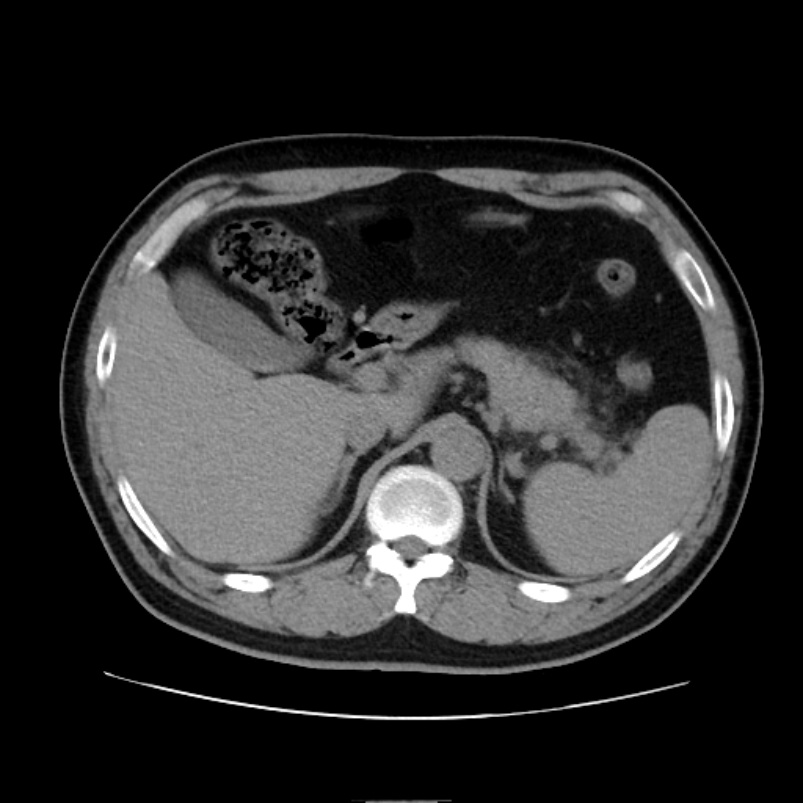

Figure 6. An 85-year-old female with a Balthazar score of 4 and CRP of 70.54 mg/L upon admission. Abdominal CT axial scan shows unclear morphology and blurred boundaries of the pancreas, with multiple fluid collections in the peripancreatic and retroperitoneal spaces. The nomogram predicts a 97% risk of composite severe outcomes. The patient developed composite severe outcomes during hospitalization and was subsequently admitted to the ICU for treatment

6. 女,85岁,入院时Balthazar评分4分,CRP 70.54 mg/L;上腹部CT轴位平扫示:胰腺形态欠清、边界模糊,胰周及腹膜后间隙多发积液表现。列线图预测复合重症风险约97%,住院期间发生复合重症结局,患者随后收治ICU并接受相应治疗